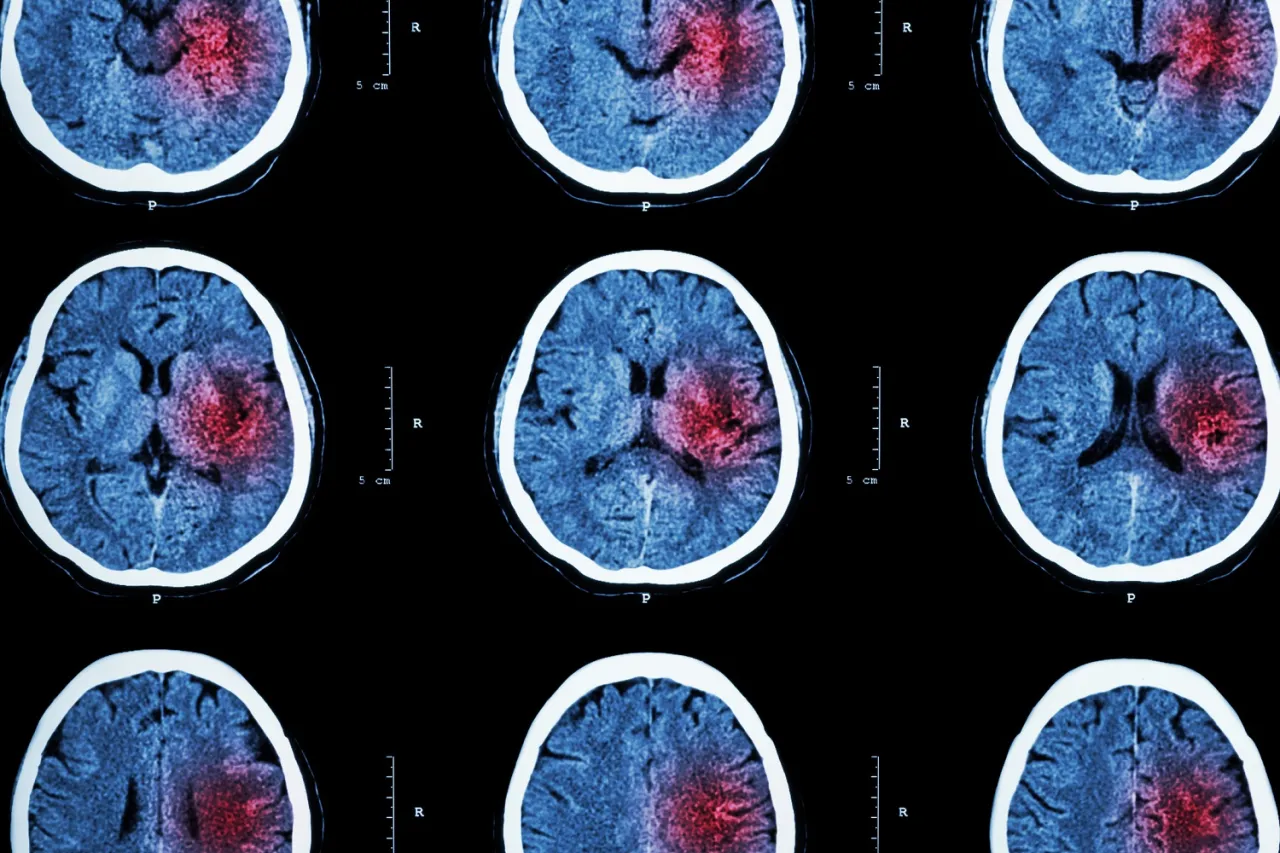

Rola tomografii komputerowej (TK) w odróżnianiu wylewu od zawału mózgu

Tomografia komputerowa (TK) głowy jest zazwyczaj pierwszym badaniem wykonywanym u pacjenta z podejrzeniem udaru. Jej główną zaletą jest szybkość i dostępność. TK pozwala na błyskawiczne odróżnienie udaru niedokrwiennego od krwotocznego. W przypadku udaru krwotocznego, wylew krwi jest widoczny na obrazie TK jako jasny obszar. Wykluczenie krwotoku jest absolutnie kluczowe, ponieważ w udarze niedokrwiennym stosuje się leki rozpuszczające zakrzep (tromboliza), które są bezwzględnie przeciwwskazane w udarze krwotocznym, gdyż mogłyby pogorszyć krwawienie.

Kiedy wykonuje się rezonans magnetyczny (MRI) i co może wykazać?

Rezonans magnetyczny (MRI) mózgu jest badaniem bardziej szczegółowym i czułym niż TK, zwłaszcza w kontekście udaru niedokrwiennego. Wykonuje się go często w dalszej diagnostyce, po wykluczeniu krwotoku. MRI jest w stanie wykryć zmiany niedokrwienne już we wczesnych stadiach udaru, nawet te, które są niewidoczne na TK. Dostarcza również bardziej szczegółowych informacji o rozmiarze, lokalizacji i wieku uszkodzenia mózgu. Jest także niezastąpiony w diagnostyce cichych udarów czy udarów żylnych, które mogą być trudne do zdiagnozowania innymi metodami.